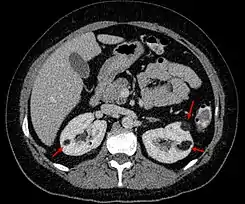

Angiomiolipomas en ambos riñones (flechas) en una tomografía axial computarizada.

Este tumor benigno es poco habitual; es el doble de frecuente en mujeres que en hombres. Se suele diagnosticar en adultos jóvenes de forma casual, en un estudio de imagen realizado por otro motivo en el 80% de los casos. Menos frecuentemente (15%) se diagnostica a raíz de una complicación hemorrágica denominada Síndrome de Wünderlich. Se suele detectar con ecografía, como una masa renal de aspecto hiperecogénico (debido a su contenido graso) pero el diagnóstico definitivo (para diferenciarlo de un tumor maligno) se establece con TAC con contraste radiológico o Resonancia Magnética sin contraste. No está indicada la biopsia por el riesgo de sangrado (al tener en su composición tejido vascular). Una vez establecido el diagnóstico de angiomiolipoma, el seguimiento se puede realizar con ecografía sin necesidad de otras pruebas de imagen. Se puede presentar de forma aislada, pero hay casos asociados a la esclerosis tuberosa o a la linfangioleiomiomatosis en cuyo caso los angiomiolipomas están presentes en ambos riñones.